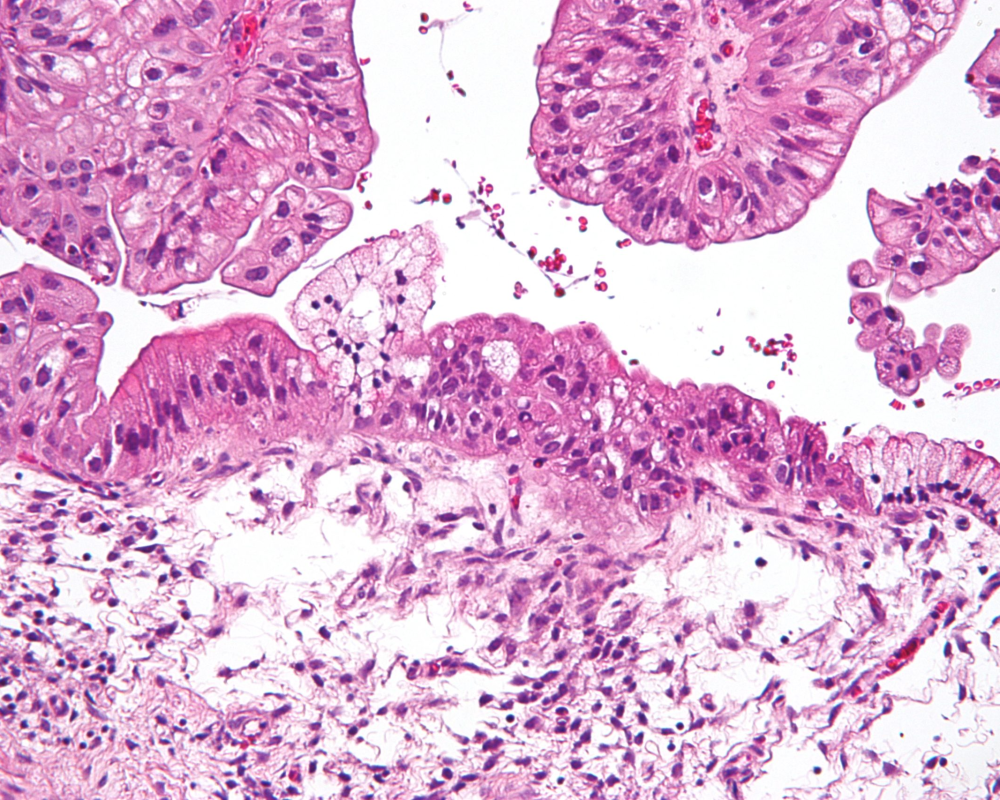

وحذر البروفيسور فنسنت لافوي، رئيس قسم جراحة أمراض النساء في مستشفى جامعة رين من سرطان بطانة الرحم الذي يتم تعريفه، على أنه تكاثر الخلايا بشكل غير منضبط، وهي عبارة عن كتلة هشة مكونة من خلايا وأوعية دموية يمكن أن تتدفق وبالتالي يمكن أن تبدأ بالنزيف بسهولة.